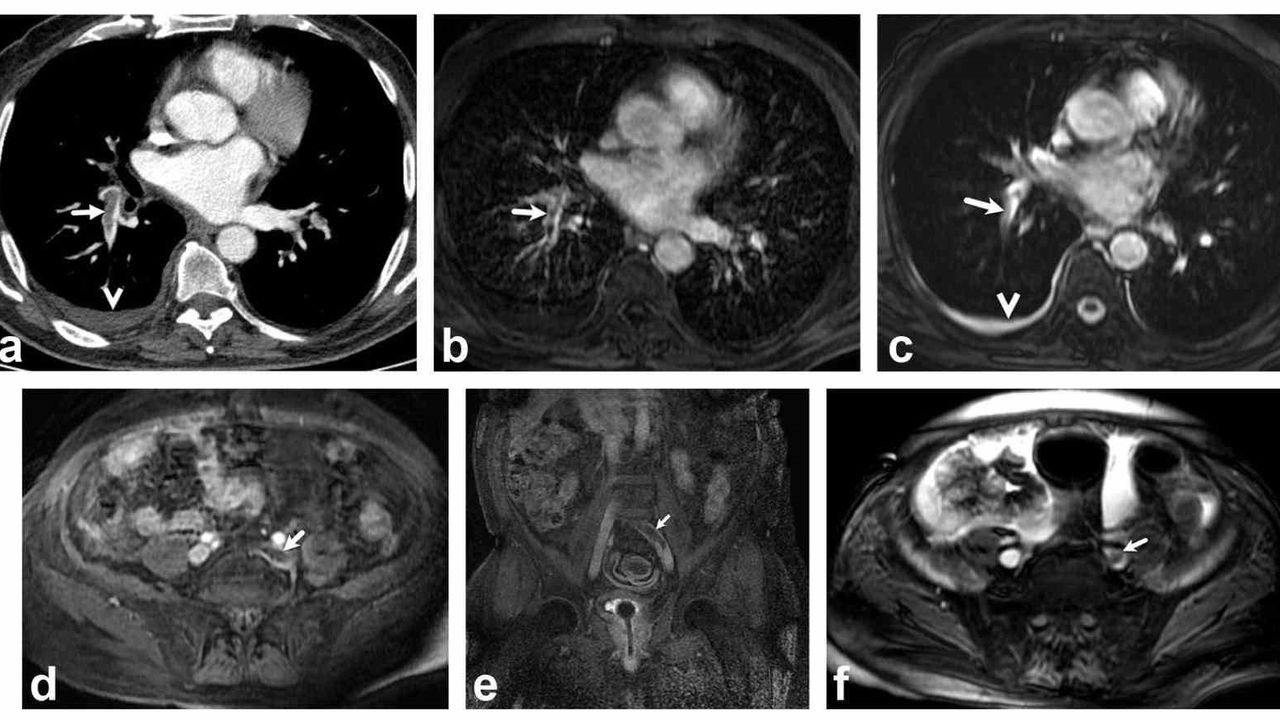

Bir dönem Denizli Tekden Hastanesinde de çalışan ve çalışmalarına ABD'de devam Dr. Nevzat Karabulut ve ekibinin yaptığı, British Journal of Radiology dergisinde yayımlanan 'Diagnostic performance of contrast-enhanced and unenhanced combined pulmonary artery MRI and magnetic resonance venography techniques in the diagnosis of venous thromboembolism' başlıklı araştırmada manyetik rezonans (MR) yöntemi kullanılarak hem akciğer damarlarının hem de pıhtının kaynağı olan bacak toplardamarlarının aynı anda, tek bir incelemede değerlendirilebileceği gösterildi. Toplam 44 hastanın incelendiği çalışmada elde edilen sonuçlar oldukça dikkat çekti.

Kontrastlı MR yöntemi, hastaların tamamında akciğer embolisini doğru şekilde tespit ederken; kontrastsız MR yöntemi de yüksek doğruluk oranına ulaştı ve önemli ölçüde güvenilir sonuçlar verdi. Bu bulgular, radyasyon içermeyen MR yönteminin pıhtı hastalığını saptamada güçlü bir alternatif olduğunu ortaya koydu. Özellikle Radyasyon riskinin daha önemli olduğugenç hastalarda ve gebelerde MR'ın güvenli ve etkili bir seçenek olabileceği vurgulandı.